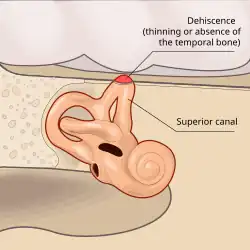

A síndrome de deiscência de canal semicircular superior, ou síndrome da deiscência do canal semicircular superior,[1] é uma condição patológica rara, descrita pela primeira vez na literatura médica em 1998, que consiste em perfurações no canal semicircular superior, dentro do ouvido.[2]

A principal causa da síndrome é o desgaste da camada óssea que recobre o canal semicircular superior. [3]